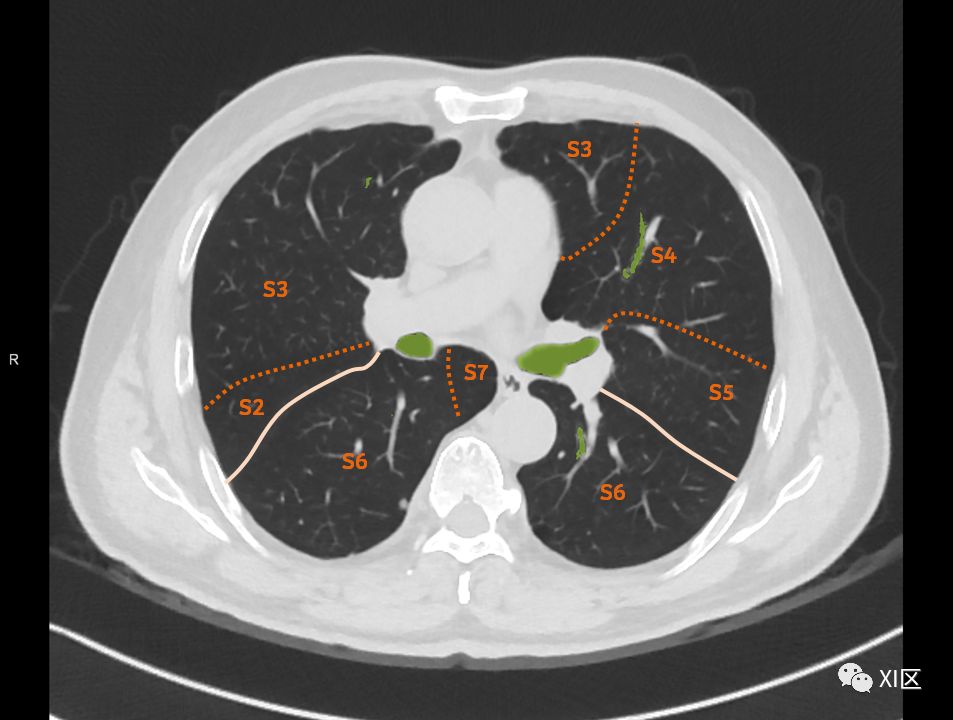

肺的断层分段示意图

在进行肺的分段时,可以上下观察浏览,沿着相应气管的走形可以更容易准确地进行分段。